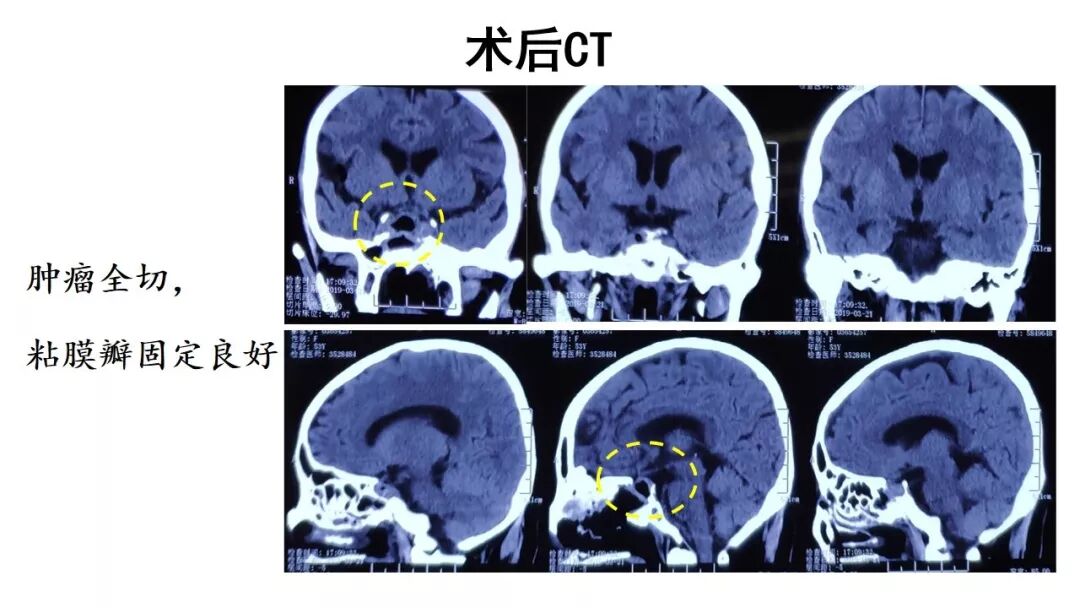

“经鼻内镜假包膜外切除垂体瘤一例(“筷子” 技术)